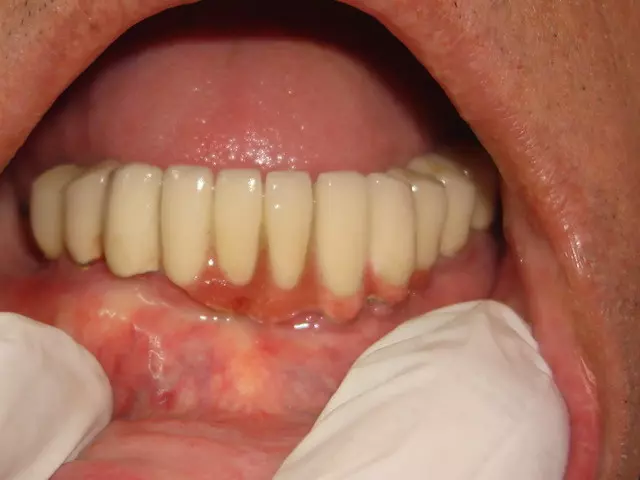

Peri-implantitis is not only common, but a serious complication. Implants have the potential to last a patient’s entire life. Peri-implantitis can lead to disintegration and early loss of implant and their supported prosthesis

Treatment of peri-implantitis include antibacterial therapy along with localised cleaning & also dental lasers are useful in treatment of infection around dental implants.

Dr Patel Uses newer design implant which have less chances of getting infection.